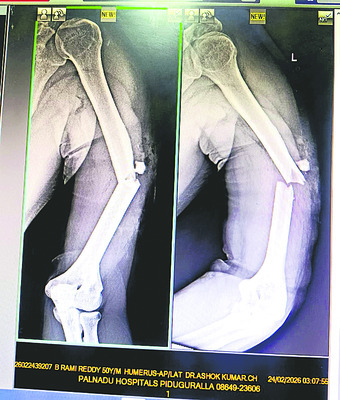

పిడుగురాళ్ల రూరల్/పిడుగురాళ్ల: అధికారం అండతో పచ్చమూకలు రెచ్చిపోతున్నాయి. వైఎస్సార్సీపీ నాయకులను టార్గెట్ చేసి.. విచ్చలవిడిగా హత్యాయత్నాలు, హత్యలకు పాల్పడుతూ రక్త దాహం తీర్చుకుంటున్నాయి. తాజాగా పల్నాడు జిల్లా జూలకల్లులో ఓ వైఎస్సార్సీపీ నాయకుడిపై టీడీపీ గూండాలు హత్యాయత్నం చేశారు. ఇనుప రాడ్లతో విచక్షణారహితంగా దాడి చేయడంతో.. ఆయన తీవ్రంగా గాయపడ్డారు. బాధితులు తెలిపిన వివరాలు.. జూలకల్లు గ్రామానికి చెందిన వైఎస్సార్సీపీ నాయకుడు బీరవల్లి రామిరెడ్డి వర్షం పడేలా ఉండటంతో సోమవారం అర్ధరాత్రి పొలానికి వెళ్లాడు. మొక్కజొన్న కండెలపై పట్టాలు కప్పి ఇంటికి బయల్దేరాడు. అప్పటికే ఆయనపై నిఘా పెట్టిన టీడీపీ గూండాలు ఇనుముక్కల సామేలు, షేక్ దాదాసాహెబ్, చల్లా మోజెస్, సింహాద్రి మరికొందరు ఒక్కసారిగా రామిరెడ్డిపై విరుచుకుపడ్డారు. ఇనుప రాడ్లు, కర్రలతో విచక్షణారహితంగా దాడి చేశారు. రామిరెడ్డి స్పృహ కోల్పోవడంతో.. వారంతా వెళ్లిపోయారు. అనంతరం కొద్దిసేపటికి అటుగా వెళ్లిన కొందరు.. రామిరెడ్డిని చూసి కుటుంబసభ్యులకు, బంధువులకు సమాచారమిచ్చారు. కుటుంబసభ్యులు వెంటనే ఘటనాస్థలానికి చేరుకొని రామిరెడ్డిని పిడుగురాళ్లలోని ఓ ప్రైవేటు ఆస్పత్రికి తరలించారు. వైద్య పరీక్షలు చేసిన డాక్టర్లు.. రామిరెడ్డి కాళ్లు, ఎడం చేయి విరిగినట్లు తెలిపారు. దీంతో కుటుంబసభ్యులు పట్టణ పోలీస్స్టేషన్లో ఫిర్యాదు చేశారు. కాగా, బీరవల్లి రామిరెడ్డిని మాజీ ఎమ్మెల్యే, వైఎస్సార్సీపీ నేత కాసు మహేష్రెడ్డి పరామర్శించారు. గురజాల నియోజకవర్గంలో గూండా రాజ్యం నడుస్తోందని మండిపడ్డారు. జూలకల్లులో ఇప్పటికే ఆరుగురిపై టీడీపీ గూండాలు దాడి చేశారని చెప్పారు. ఇంకా మూడేళ్లు మాత్రమే ఉందని.. దాడులు చేసే వారు, చేయించే వాళ్లు ఇంతకింతా అనుభవించే రోజులు వస్తాయన్నారు. చట్టపరంగా శిక్షలు పడే రోజులు దగ్గరలోనే ఉన్నాయని హెచ్చరించారు.